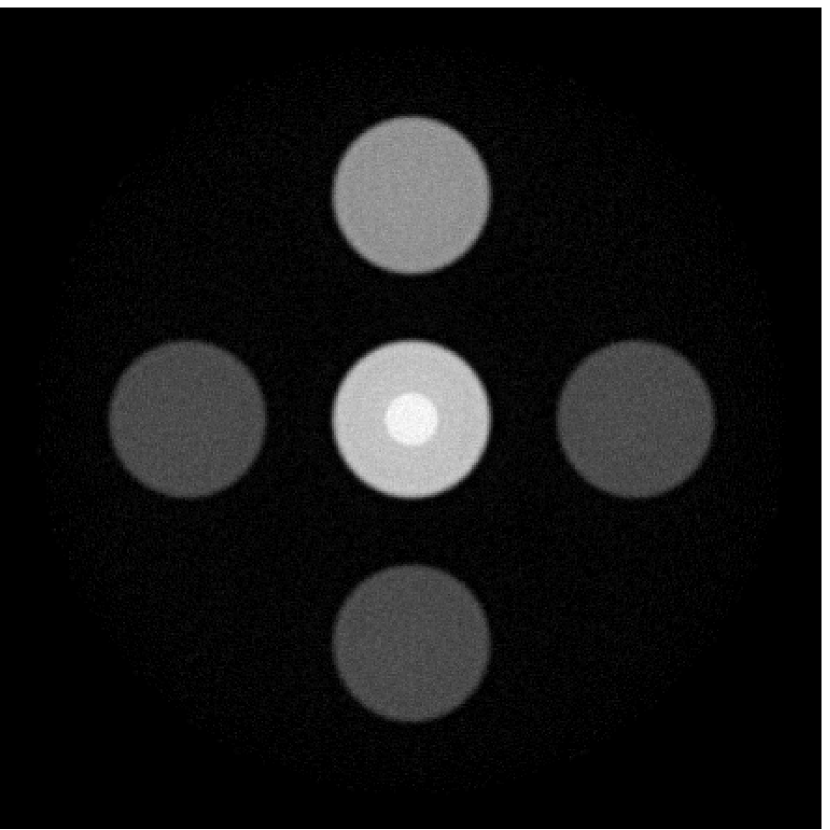

The images and EIRs reconstructed by use of the VP algorithm that was based on the 2D imaging model that neglected the SIR are shown in Figures 15 and 16. The latter figure contains results corresponding to different values for the regularization parameter . From Fig. 15, it can be observed that use of the conventional iterative method that utilized the measured EIR resulted in distortions and loss of details in the reconstructed images. Use of the VP algorithm improved the contrast and the details in the reconstructed images (Fig. 15(c) and 16(a)). Furthermore, the images reconstructed by use of the VP algorithm had a more uniform background.

In Figure 17, the results corresponding to use of the 3D imaging model that incorporated SIR effects are shown. The EIR estimated by the VP algorithm is also shown. In Figure 18, images and EIRs reconstructed by use of the VP algorithm with different regularization parameters values are shown.

Similar to the case described above where the transducer SIR was neglected, these results reveal that use of the VP algorithm can produce images with a cleaner background and enhanced spatial resolution than yielded by use of a conventional iterative algorithm that employed the measured EIR. For example, detailed information regarding the vessels near the organ’s periphery was better preserved by the VP algorithm than by the conventional iterative algorithm. These images corroborate our assertion that the VP algorithm can significantly reduce the artifacts and distortions in the reconstructed image. It is also worth pointing out that, unlike the numerical phantom studies, the artifacts and distortions in the images may be caused not only by the inaccurate EIR but also by other factors, such as neglecting acoustic heterogeneities and the variation of the EIRs among the elements of the transducer array. In such cases, the EIR estimated by the VP algorithm represents an effective system impulse response that minimizes the inconsistency between the measured data and the imaging model.